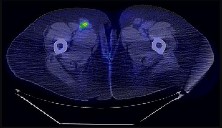

Figures 9a through 9d are the anteroposterior and lateral radiographs, CT scan, and technetium bone scan of a 12-year-old boy who has experienced 7 months of pain in his lower leg. The pain limits his ability to participate in sports and he is having difficulty sleeping. He is afebrile, and laboratory study findings including an erythrocyte sedimentation rate, C-reactive protein, and complete blood count are within normal limits.

The images and clinical history support a diagnosis of osteoid osteoma, which most commonly occurs in adolescence. Although these lesions can be seen in any bone, they are usually located in the femur and tibia. The significant inflammatory response to this tumor is secondary to high levels of prostaglandin production. Characteristic night pain is relieved with nonsteroidal anti-inflammatory drugs (NSAIDs) or by aspirin.

Radiographic images show thickened bone and a small central nidus. Thin-cut CT scan is the imaging of choice to visualize the nidus. A bone scan is associated with uptake but is not specific. Treatment options include expectant management with NSAIDs and observation under the premise that these lesions eventually burn out. Contemporary treatment involves RFA. Historically, these lesions were treated with en bloc resection; however, this technique has largely fallen out of favor because of the high efficacy and comparative low morbidity associated with RFA.

When an osteoid osteoma occurs in the spine, it is located in the posterior elements, and paraspinal pain and scoliosis often are present.